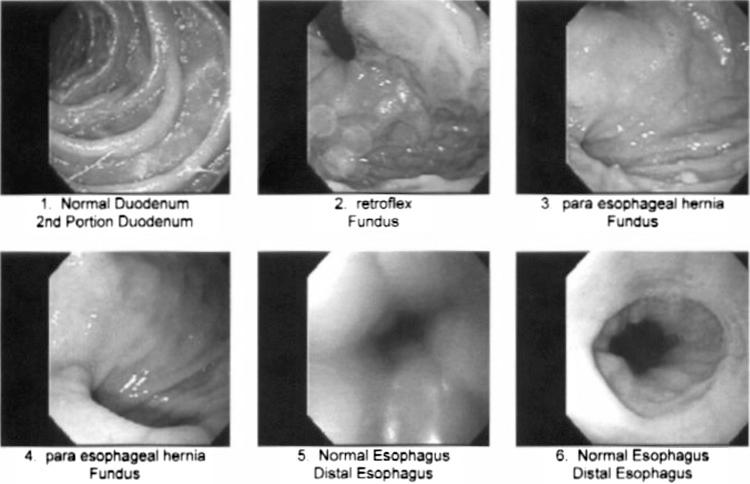

The patient is a 45-y-old male presenting with a 4-mo case of dysphagia, small amounts of regurgitation, and abdominal pain but no other symptoms.

RESULTS

The patient was diagnosed with a gastric diverticulum, which was subsequently successfully treated with a laparoscopic gastric diverticulectomy.

该患者被诊断为胃憩室,随后通过腹腔镜胃憩室切除术成功治愈。